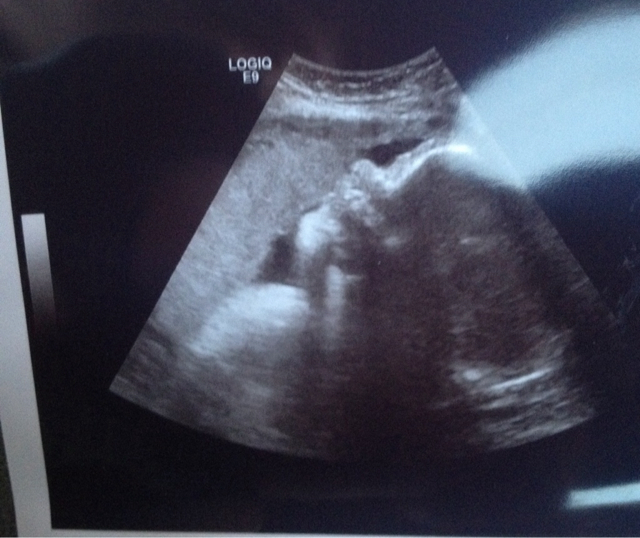

skull theory can be used at any stage its how anthropologists and forensic departments identify gender of remains. Its "guessing" on pregnancy related to the actual science but sometimes there is a strong enough skull. This one would fall into the girl category. But remember its no where close to a science for pregnancy like it is on an adult skull.

I think it may be Boy.... as the Jaw is not square and the upper part of forehead is not round....